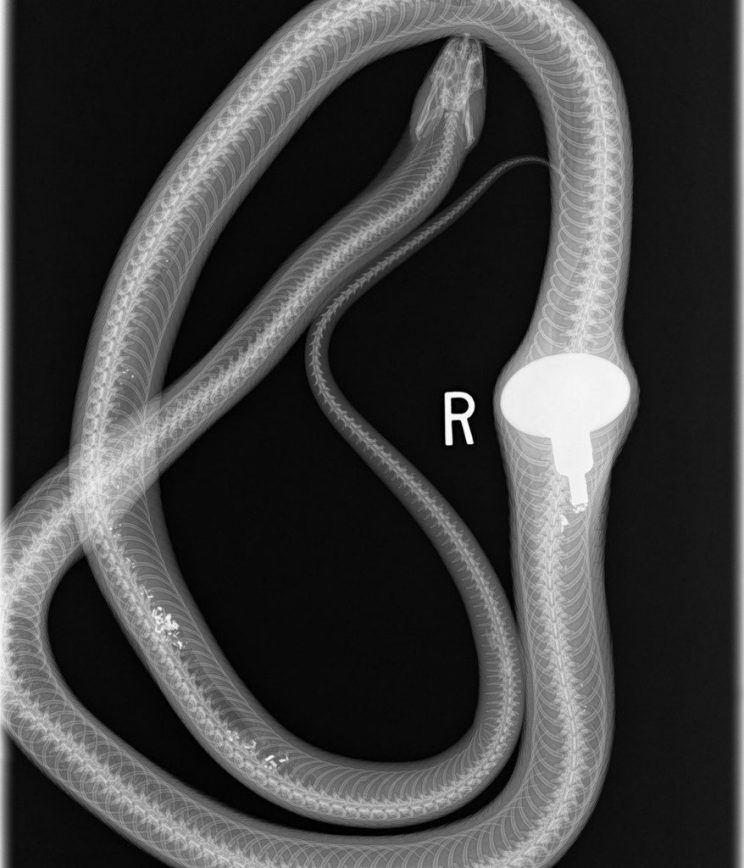

Seperti dilansir brilio.net dari siakap keli, seekor ular didapati memiliki tonjolan yang kontras di bagian perutnya. Setelah diperiksakan diketahui reptil itu telah menelan gagang pintu yang ukurannya seperti telur ayam. Peristiwa memilukan ini terjadi di Missouri, Amerika Serikat.

Mengetahui ada yang tak beres dengan ular itu, sang pemilik peternakan segera membawanya ke rumah sakit hewan. Tubuh ular diperiksa dengan X-rays. Ular menjalani operasi bedah perut untuk mengeluarkan benda itu.

2. Ketika dilakukan X-ray.

3. Tampak gagang pintu yang ditelannya.